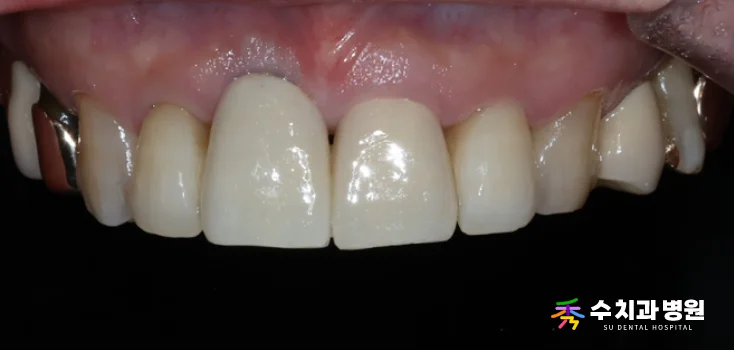

✨ 치료 후 (After)

[치료 후 사진] (촬영일: 2025년 09월)

앞니 임플란트크라운 치료가

성공적으로 마무리되었습니다.

아래로 처져 보이던 잇몸 라인이

가지런하게 회복되었습니다.

어떤 것이 임플란트인지 모를 정도로

자연 치아와 완벽한 조화를 이룹니다.